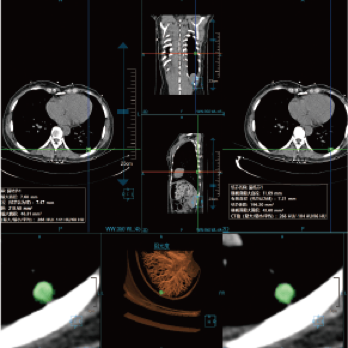

High-power generator delivers high mA output for rapid scanning of complex anatomy and large coverage areas, boosting scan speed while enhancing image signal-to-noise ratio and minimizing artifacts

Wide detector expands single-rotation coverage, shortens exam time, reduces motion artifacts, decreases radiation dose, and saves tube exposure time while effectively lowering operating costs